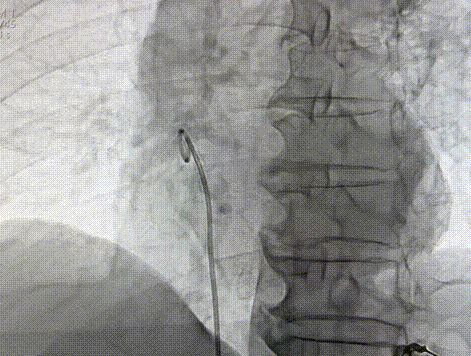

通过股静脉穿刺,建立血管通路,经导丝送入猪尾导管至右心房,分别在RAO 30°和LAO 30°进行右心耳造影,确认目标位置。

右心耳RAO造影